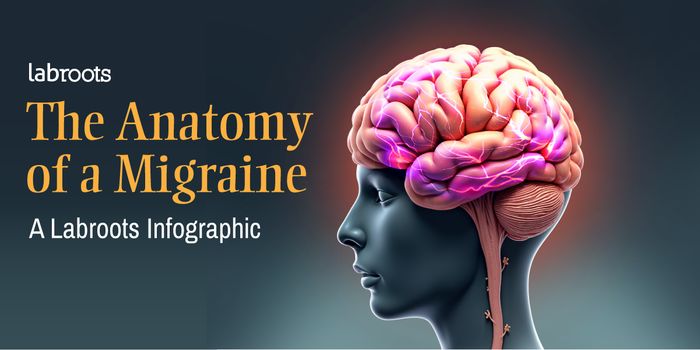

FEB 14, 2017InfographicsYou are exercising, focusing only on what you are doing and what is coming next. All of the sudden, piercing pain hits y ...